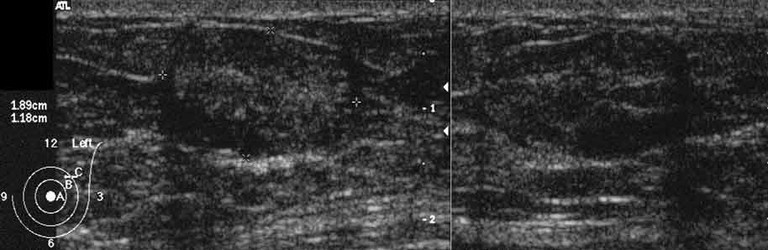

When to aspirate a breast cyst demonstrated on US

• A cyst should be aspirated if there are internal echoes (ie. when it is unclear whether it is a cyst or solid) or if the patient seeks relief from symptoms.

• Cysts get larger and smaller, come and go. –> Enlargement of a simple cyst is not in and of itself an indication for aspiration.